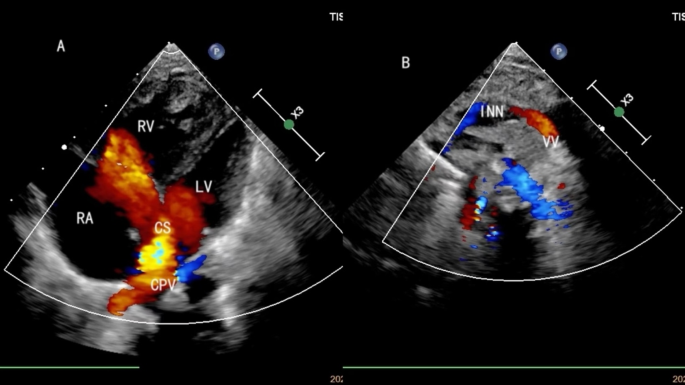

All 48 cases underwent echocardiographic examination to evaluate the pulmonary venous drainage pathways, the presence of obstruction, associated malformations, and cardiac function. Among the 15 supracardiac types, nine cases drained into the innominate vein and six into the superior vena cava (SVC) (Fig. 1). There were 13 single vertical vein and 2 cases of double vertical veins. In the 20 cardiac cases, 17 CPVs drained into the RA via the coronary sinus (CS) (Fig. 2), two CPV drained directly into the RA, and one had four pulmonary veins draining separately into the RA. Among the 10 infracardiac cases, eight cases had CPVs that drained into the portal vein via a vertical vein, one drained into the hepatic vein, and one drained into the inferior vena cava via ductus venous (Fig. 3). In the three cases mixed-type cases, all of them combines both supracardiac and cardiac types (Fig. 4).

The echocardiography of mixed TAPVC. (A) The CPV drains into RA via CS. (B) The other pulmonary vein drains into innominate vein via vertical vein.